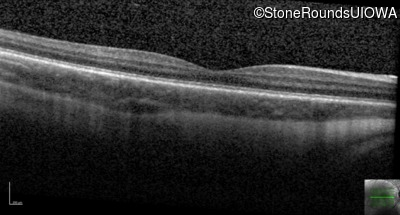

Age at visit: 7 years

This 7 year old boy had nystagmus first noticed at 4 months of age.

Age at visit: 10 years

Blue Cone Monochromacy L/M OPSIN Cluster Promoter Deletion LCR   XL